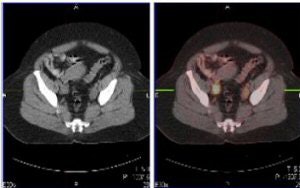

| Above and below, representative images of a 39-year-old patient, currently undergoing treatment, with FIGO stage IB2 squamous cell carcinoma of the cervix. Pretreatment FDG-PET/CT identified an FDG-avid cervical tumor mass plus bilateral iliac and right common iliac metastatic lymphadenopathy. Images courtesy of Dr. Julie Schwarz, Ph.D. |

Twenty-five patients with advanced-stage cervical cancer were included, all of whom were treated with chemoradiation. Whole-body FDG-PET scans were done and co-registered with CT scans. Twenty-eight pretreatment tumor biopsies were done, and pathologic review confirmed the presence of invasive cancer in 26 of 28 cases.